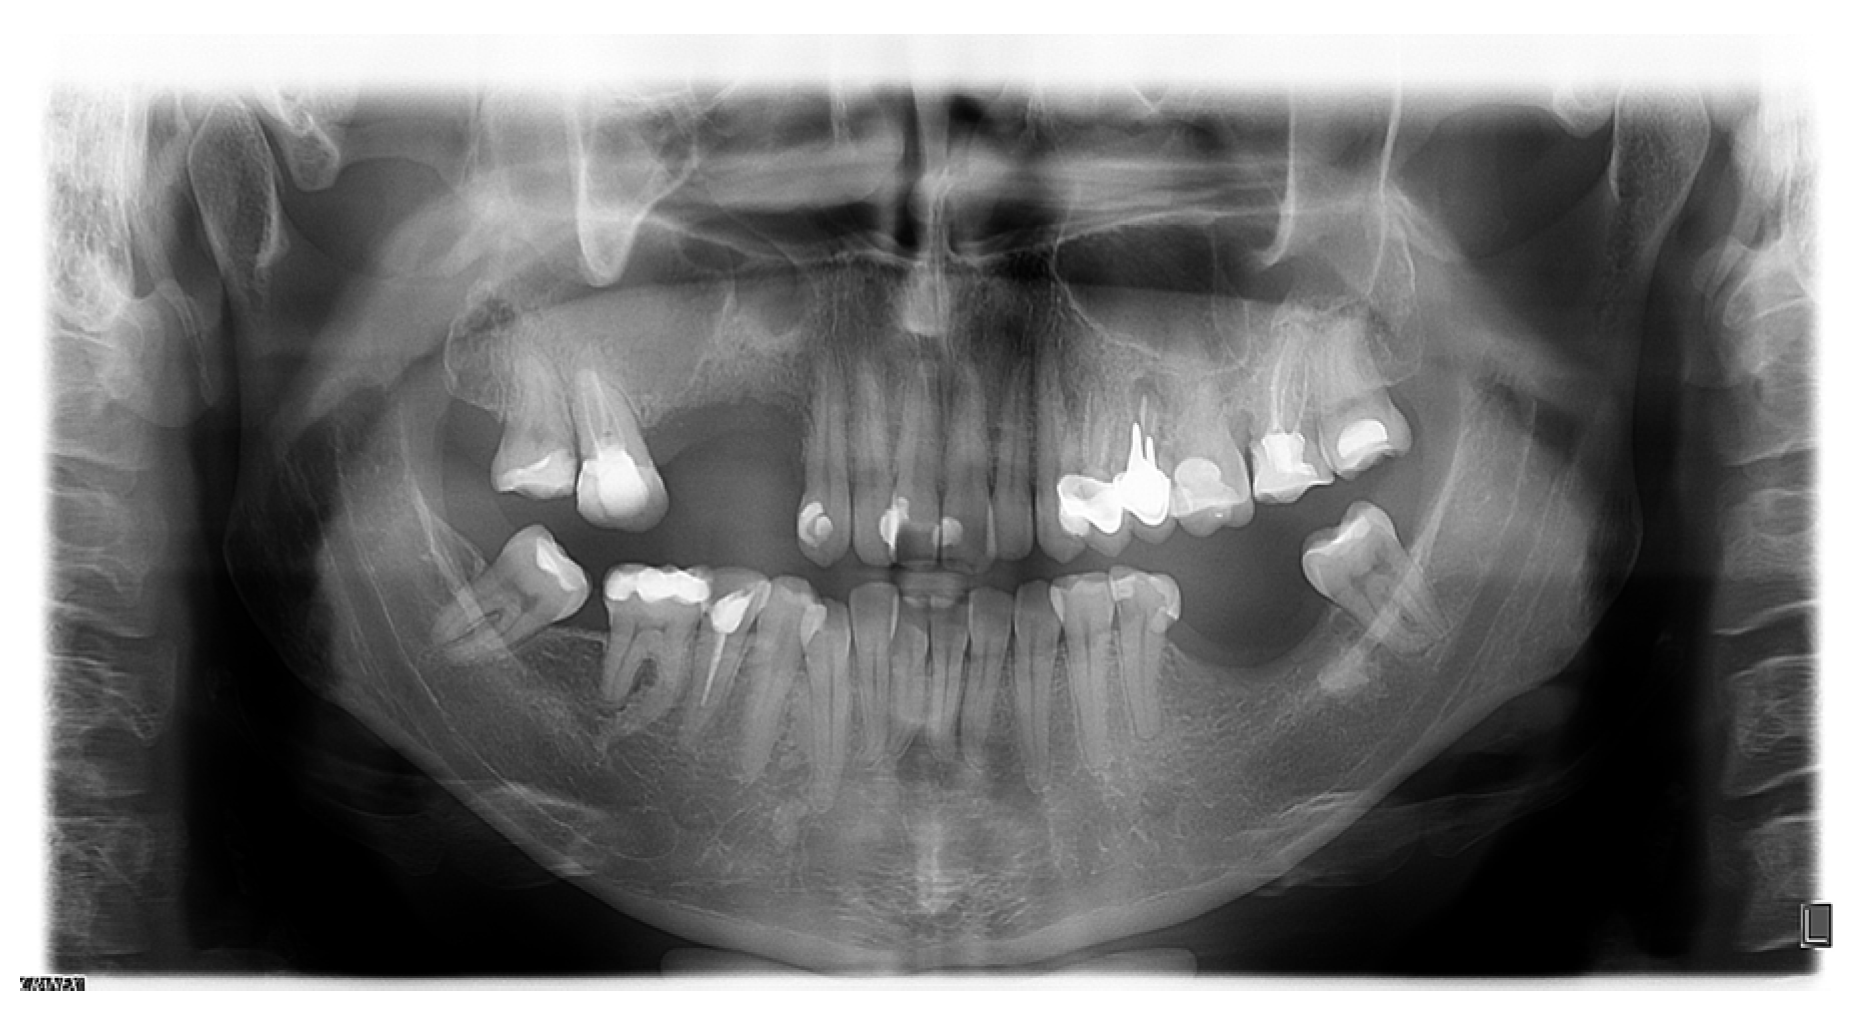

Concurrent Onset of Central Retinal Vein Occlusion and Inflammation of a Large Maxillary Odontogenic Cyst: Case Report and Analysis

2. Case Presentation